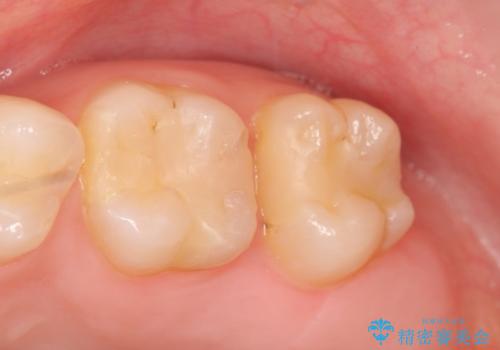

- 左上奥歯がしみるといらっしゃった方の症例です。

左上7近心の虫歯は歯茎より深く、歯茎を下げるため歯周外科を行いました。

術後歯肉の回復を待ち、左下6、7ともにセラミックインレーによる修復を行いました。